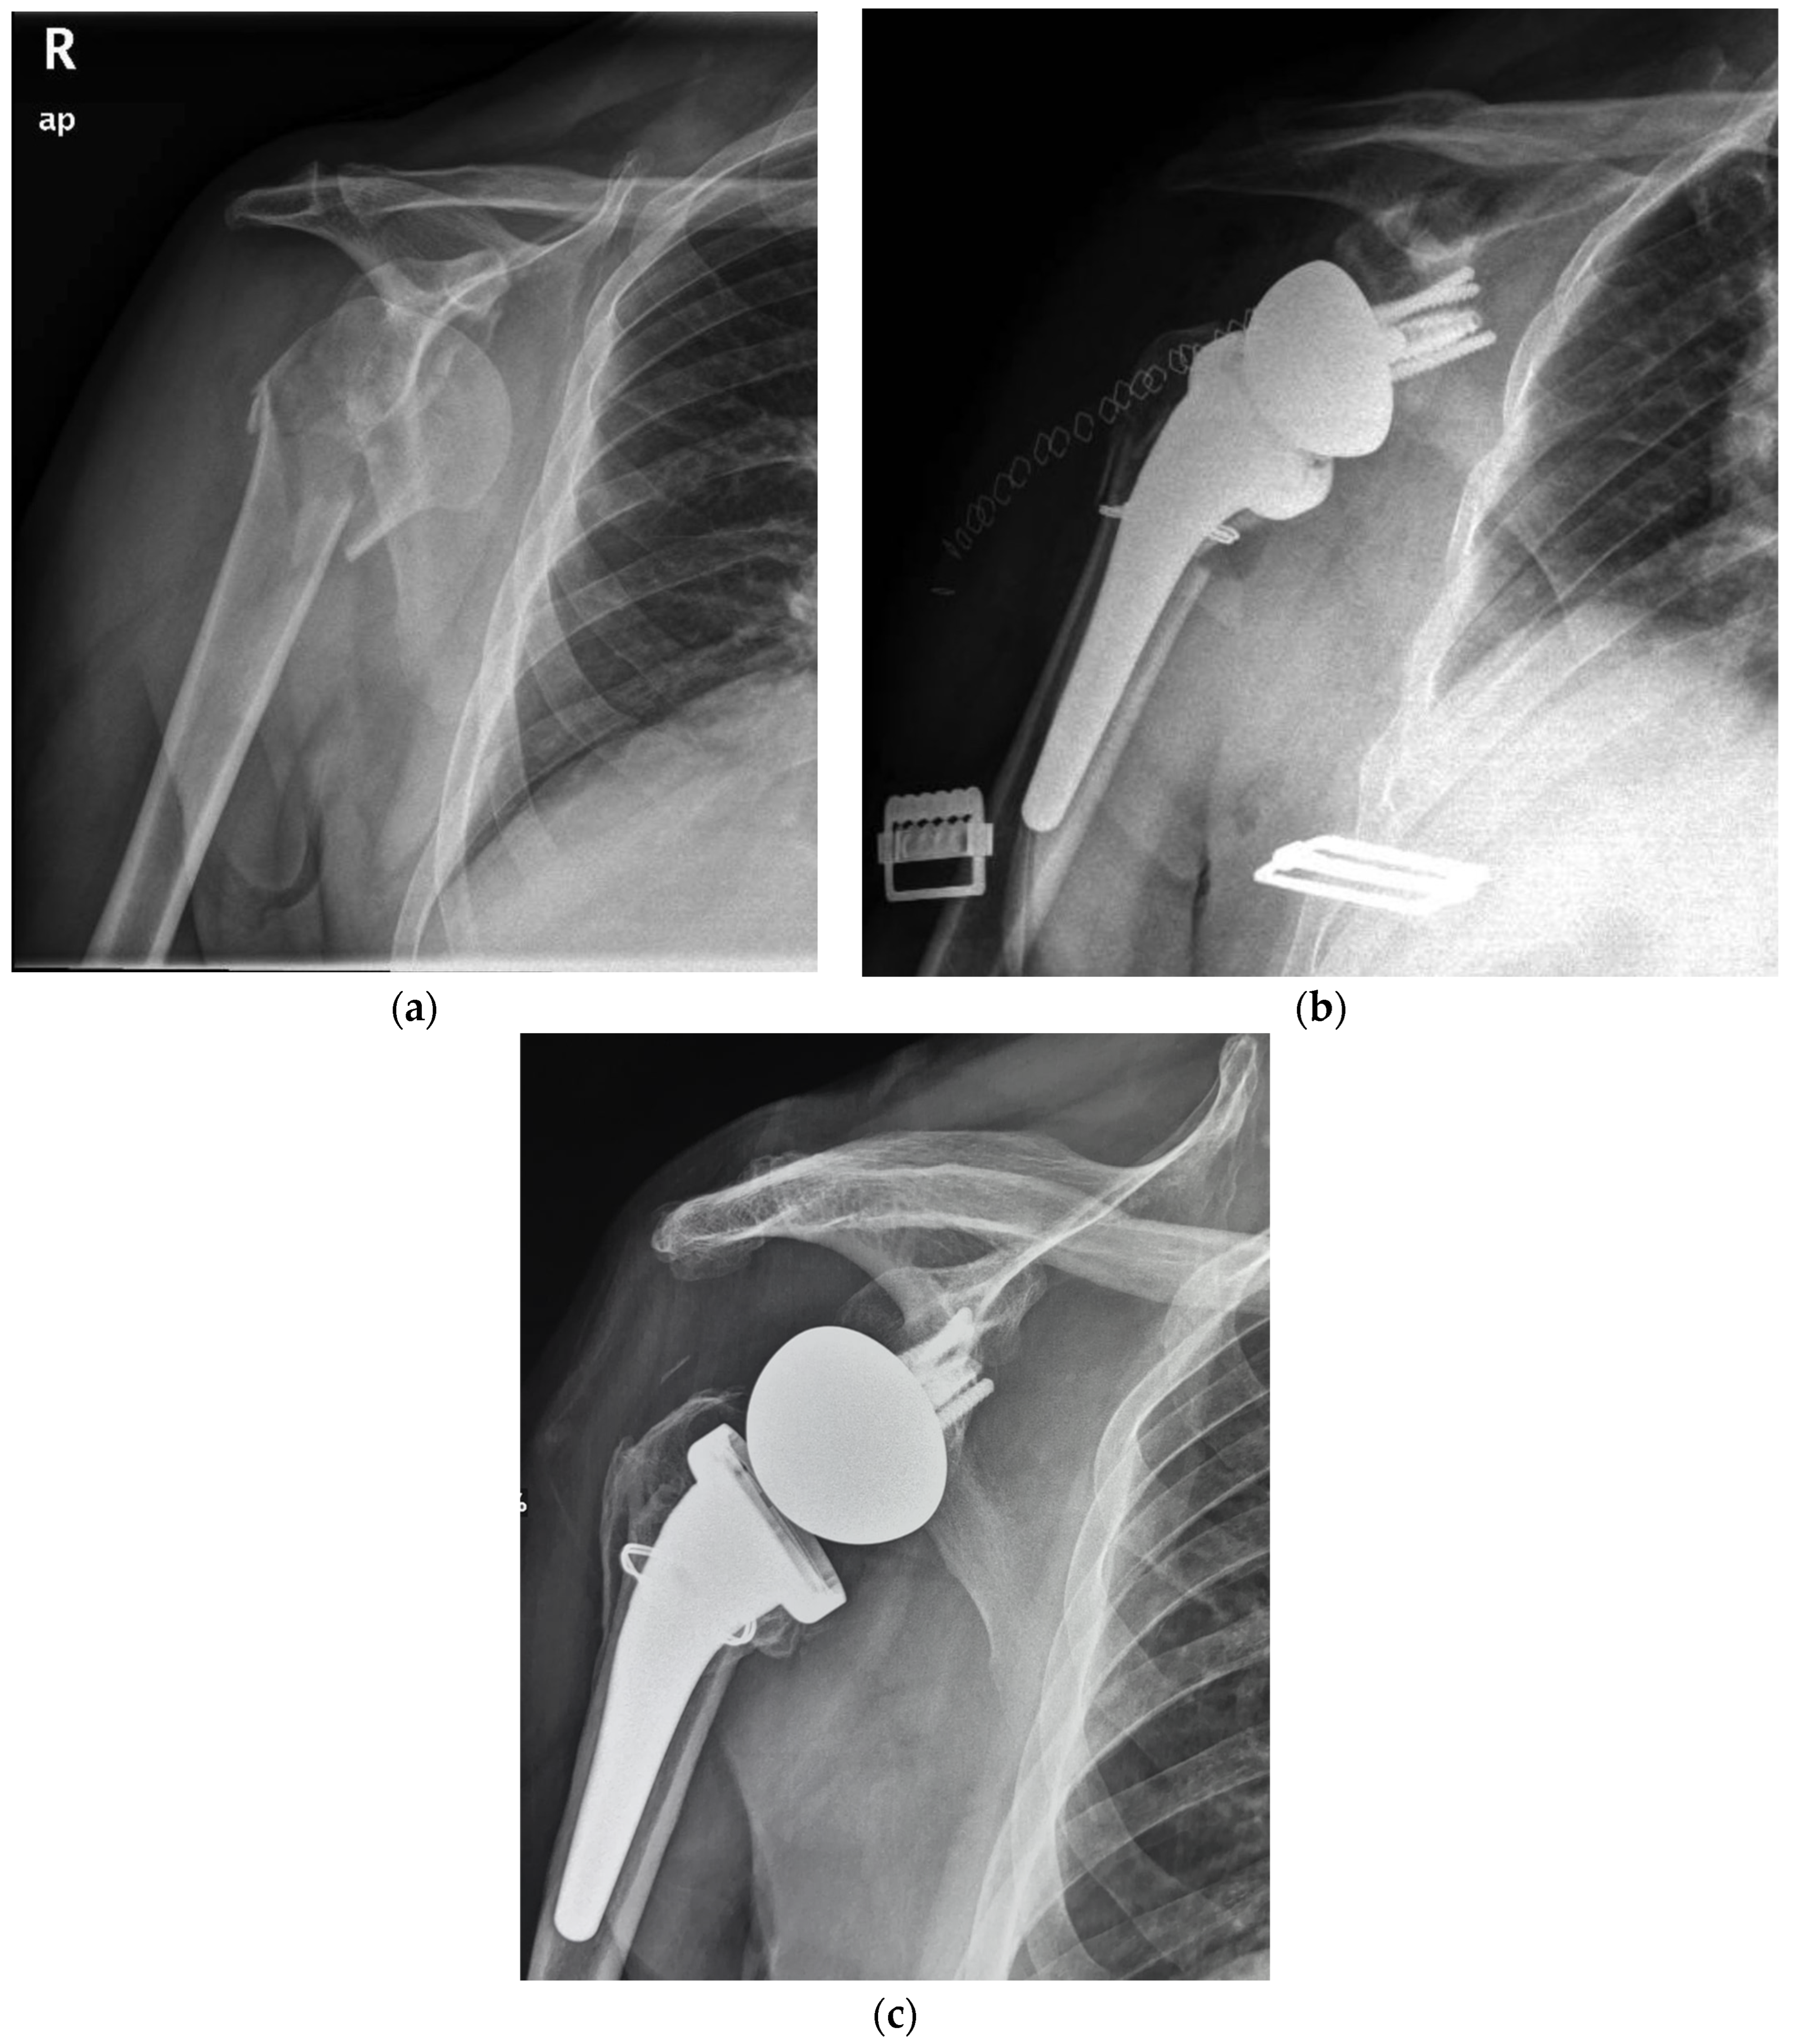

Figure 1.

(a) Preoperative radiographic image of right shoulder showing acute (Neer three-part) proximal humeral fracture with calcar involvement. (b) Immediate postoperative film of right shoulder showing calcar fragment fixation with steel wire cerclage. (c) 5.7 years postoperative film of right shoulder showing stem subsidence and healing of tuberosity and medial calcar.

The overall complication rate at the final follow-up was 28% (19 patients, Table 3). Postoperative complications included tuberosity non-union in ten patients, scapular notching in two patients, radiolucent lines in two patients (one in group A and one in group B), subsidence in three patients (one for group A, 5.5% and two for group B, 4%), heterotopic ossification in one patient and superficial infection in one patient. The subsidence observed (Figure 1c) was never associated with any symptoms, pain, or evident implant loosening throughout the follow-up. Bone healing of the medial calcar fragment was always observed with heterotopic ossifications in two patients.

The experience of cementless fixation thus far published has regarded mainly three-, four-, and rarely two-parts PHFs. No mention may be found on more severe fracture patterns, such as those with a medial calcar fragment [23]. Moreover, most of the series have employed standard or long stems with a press-fit achieved often in the diaphyseal bone. Our series supports the safety and viability of RTSA with a cementless and metaphyseal stem’s fixation for two-, three-, and four-part PHFs but as well in selected fractures with a calcar fragment that is sizable to be fixed with steel wire cerclage (Figure 1 and Figure 2). At a minimum follow-up of five years, the clinical outcomes (ASES score of 89.2, Simple Shoulder Test score 91.1 and NRS pain of 0.8) were satisfactory and supported by the comparison with a control group of patients without the calcar fragment (ASES score of 91.6, Simple Shoulder Test score 90.4 and NRS pain of 0.5). For both groups, the results are likewise comparable to those achieved by other series with either cementless or cemented stems.